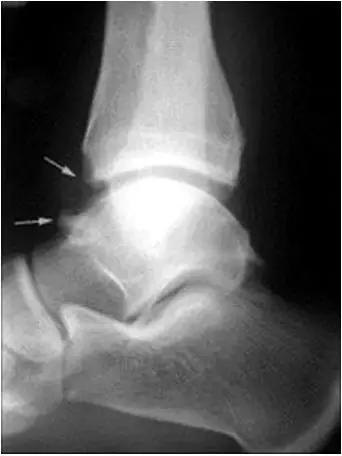

- 放射学表现主要为胫骨前下缘与距骨颈部前上缘鸟嘴样骨刺形成。

放射学表现主要为胫骨前下缘与距骨颈部前上缘鸟嘴样骨刺形成

- Ⅰ度:滑膜撞击,X线片显示有炎性反应,骨刺大小为3mm;

- Ⅱ度:骨软骨反应性骨赘>3mm;

- Ⅲ度:严重的外生骨赘,可伴有或不伴有碎裂, 在距骨背侧可见继发性骨赘,常伴有骨赘的碎裂;

- Ⅳ度:距骨和胫骨关节骨性关节炎改变。

- 踝关节正侧位X 线平片,侧位片均显示距骨后方有三角形或椭圆形的距后三角骨。部分病例伴有轻度的踝关节骨性关节病。